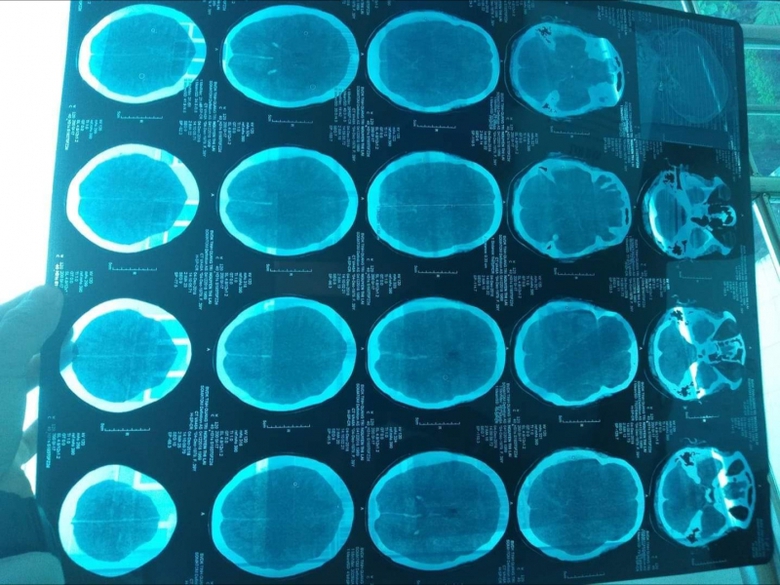

Bác sỹ lý giải chị Lài tử vong do chấn thương sọ não nặng |

Liên quan đến vụ việc, bác sĩ Trương Xuân Nhuận, Phó Giám đốc Bệnh viện Đa khoa tỉnh Quảng Trị cho biết, các bác sĩ đã làm đúng quy trình, đúng chuyên môn và nhanh chóng. Chấn thương vùng mặt gây chấn thương sọ não kín rất nguy hiểm khiến chảy máu dưới màng cứng bán cầu não phải, xuất huyết dưới nhện và phù não 2 bán cầu.

Chị Lài được chẩn đoán ngừng tuần hoàn hô hấp do chấn thương sọ não nặng, không có chỉ đạo phẫu thuật, điều trị theo hướng hồi sức tích cực. Nếu không có sốc phản vệ thì trường hợp này tỷ lệ tử vong cũng rất cao.

“Không phải do bác sĩ dùng thuốc bậy hoặc làm không đúng chuyên môn. Đó là phản ứng dị ứng của cơ thể đối với dị nguyên hoặc thuốc, mà thuốc đó không thể không dùng được. Hôn mê này là do chấn thương sọ não nặng thể hiện bằng lâm sàng theo dõi. Mặc dù bệnh nhân tim trở lại bình thường, phổi trở lại bình thường, huyết áp lên, bệnh nhân tỉnh mà hình ảnh CT và scanner là có tổn thương não”, bác sỹ Nhuận lý giải.